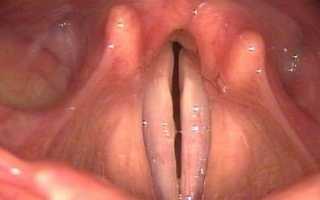

При любом обследовании пациента с парезом гортани первым этапом является микроларингоскопия, которая позволяет оценить положение голосовых связок, а также расстояние между ними и их состояние. Это исследование помогает определить состояние слизистой оболочки гортани, выявить наличие различных воспалительных процессов, включая кровоизлияния.

После изучения предъявленных жалоб и проведения внешнего осмотра шеи и ротовой полости, лечащий врач решит назначить одно из следующих обследований: ларингоскопию, которая включает изучение положения голосовых связок, выявление воспалительных процессов, оценку состояния слизистой оболочки гортани и ее целостности, томографию, рентгенографию и электромиографию для оценки состояния мышц. Для определения уровня нарушения голосовых функций также могут использоваться фонография, стробоскопия и электроглоттография.

- исследование ларингоскопией – используется для оценки положения голосовых связок, расстояния между ними, выявления воспалительных процессов или кровоизлияний